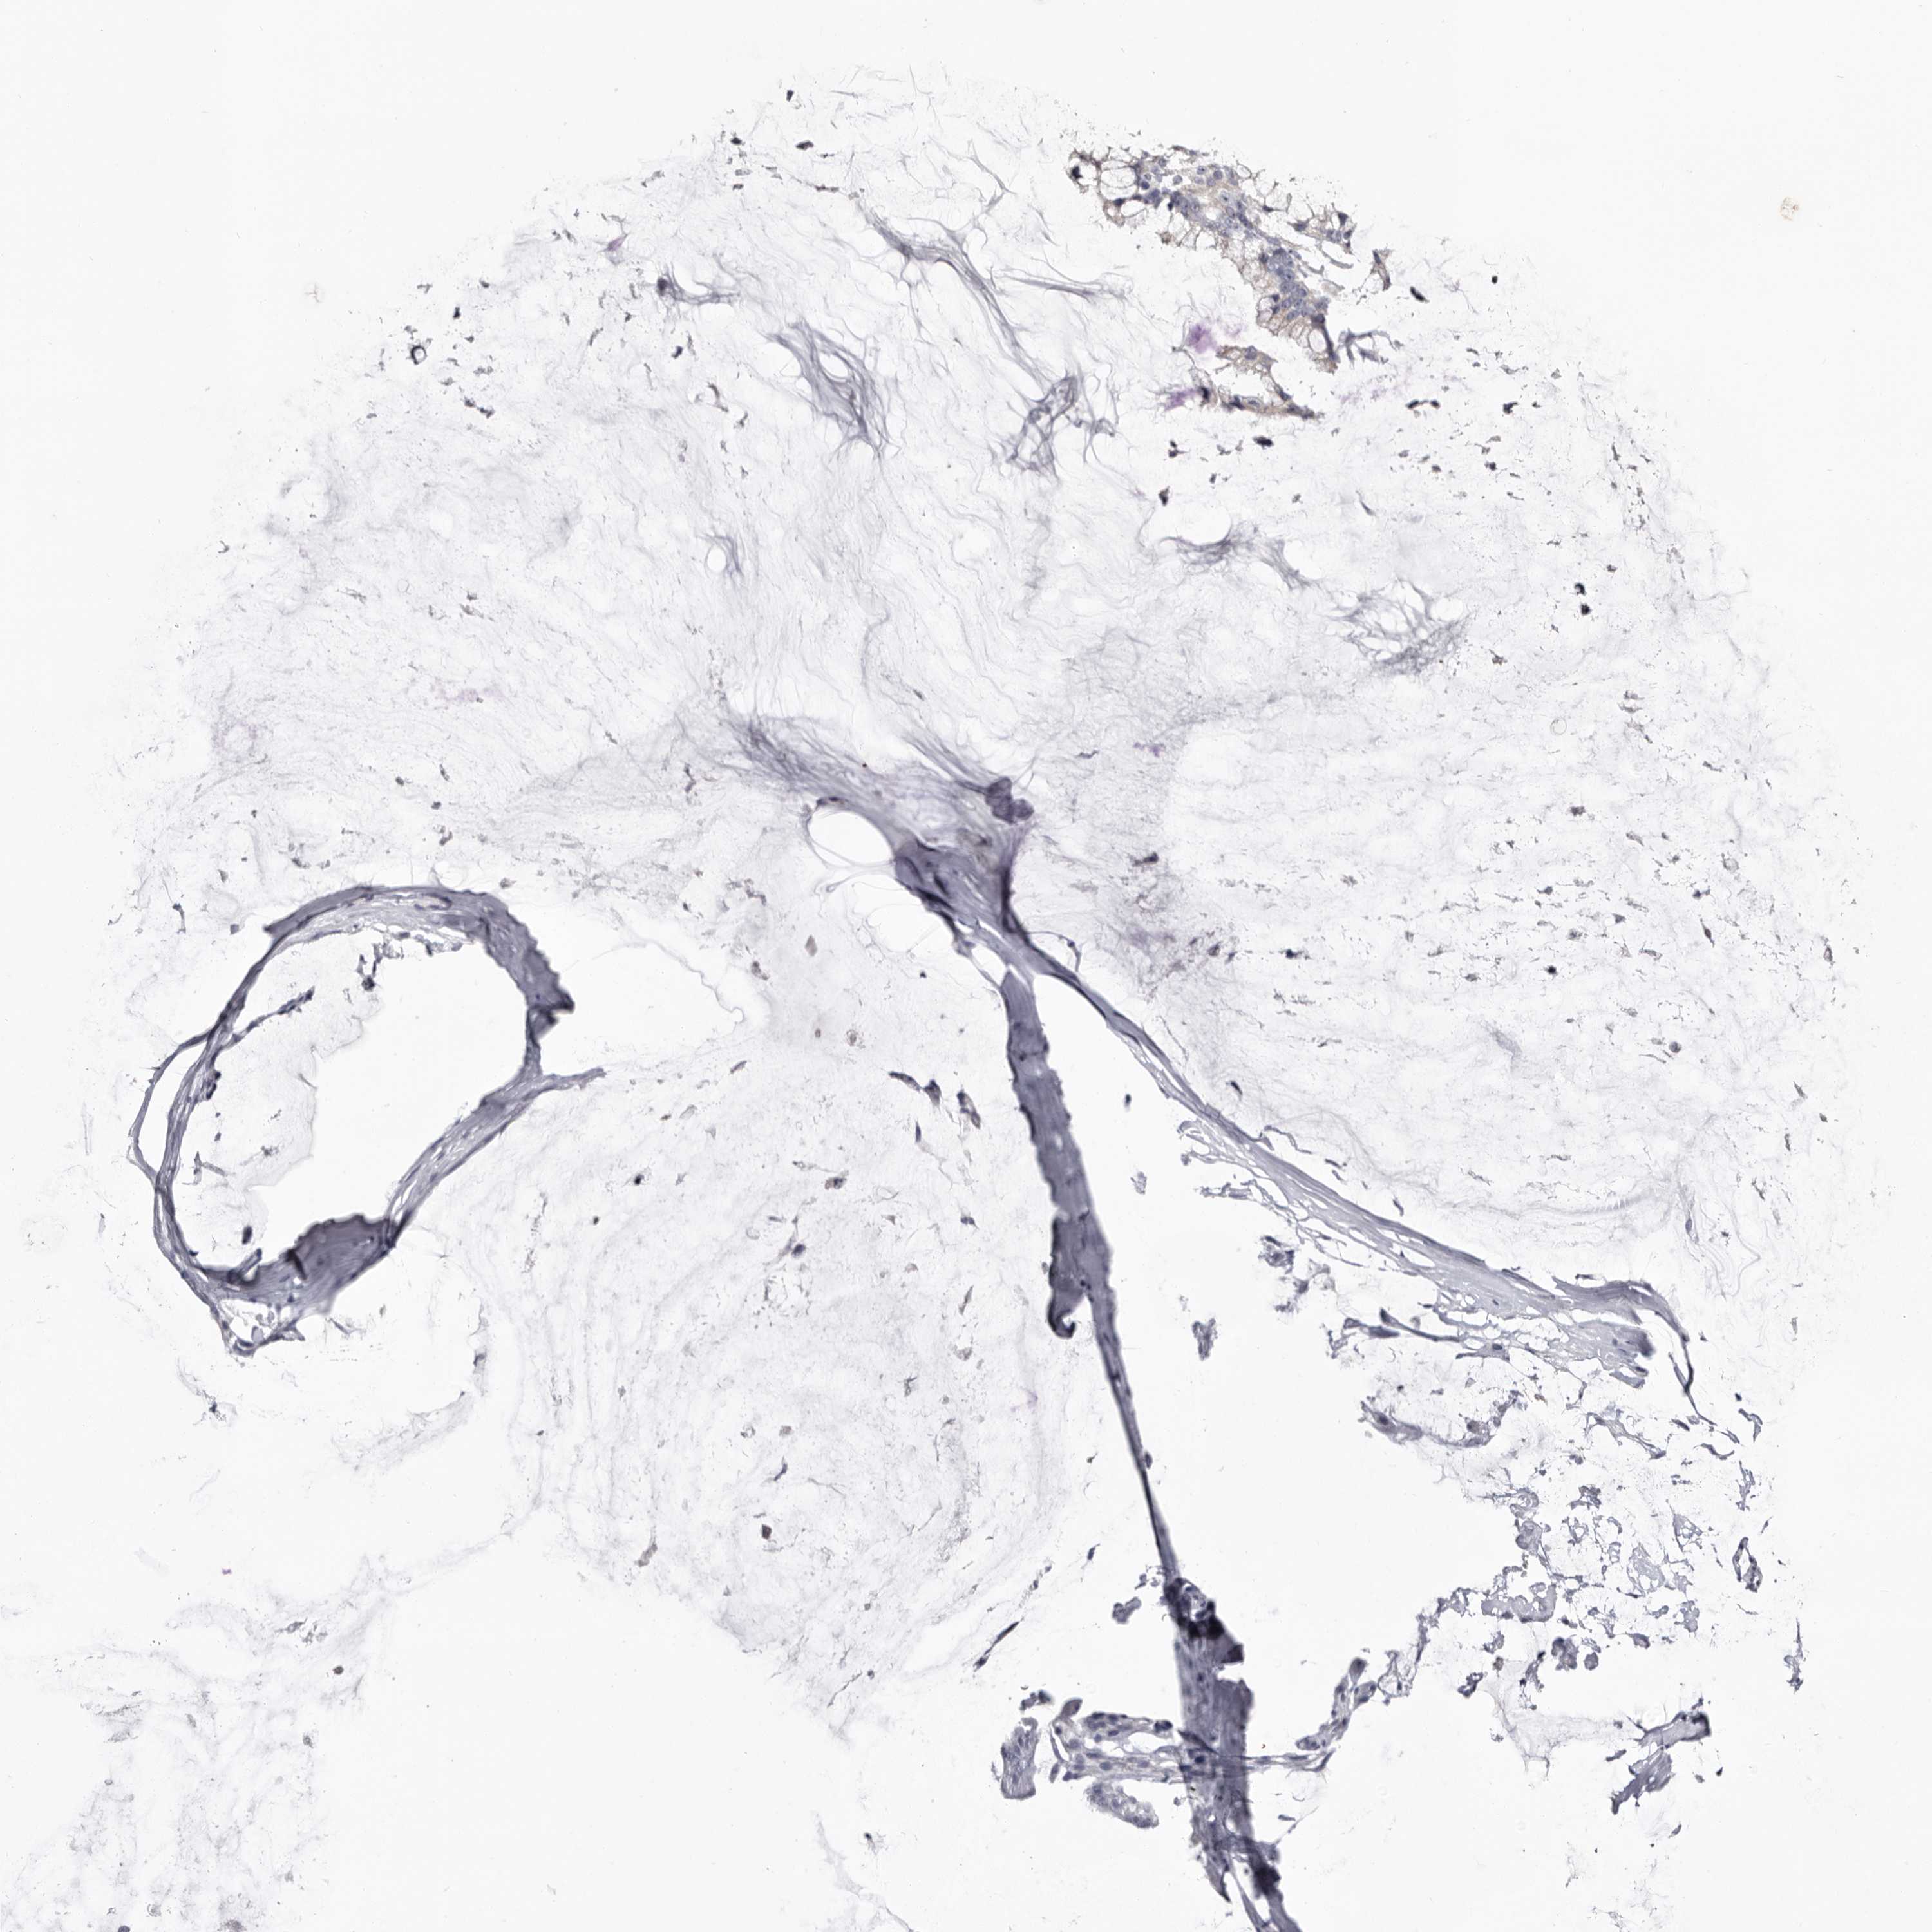

OVARIAN CANCER - Protein expressioni

A mouse-over function shows sample information and annotation data. Click on an image to view it in a full screen mode. Samples can be filtered based on level of antibody staining by selecting one or several of the following categories: high, medium, low and not detected. The assay and annotation is described here.

Note that samples used for immunohistochemistry by the Human Protein Atlas do not correspond to samples in the TCGA dataset.

Antibody stainingi

Antibody staining in the annotated cell types in the current human tissue is reported as not detected, low, medium, or high, based on conventional immunohistochemistry profiling in selected tissues. This score is based on the combination of the staining intensity and fraction of stained cells.

Each image is clickable and will lead to virtual microscopy that enables deeper exploration of all samples and also displays staining intensity scores, fraction scores and subcellular localization as well as patient and tissue information for each sample.

Antibody HPA007845

Antibody HPA026823

Antibody CAB015170

Cystadenocarcinoma, serous, NOS

Carcinoma, endometroid

Cystadenocarcinoma, mucinous, NOS

Carcinoma, NOS